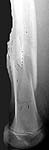

Date: Wed, 20 Jun 2001 23:19:13 -0700

From: Carlo Bellabarba

alex,

here's a recent Ender example with three-month followup. sorry about the

quality of the injury image--there were better outside films that have since

disappeared. I still think this technique is useful, even in rotationally

unstable patterns such as this one. i take the nails out at 6 mos, and leave

them a little proud on purpose (this 10 year-old is a bit of chunkster so

they don't bother him) and suture them down so that they don't back out

more.

it aren't fancy, but it's quick and seems to work.

carlo bellabarba